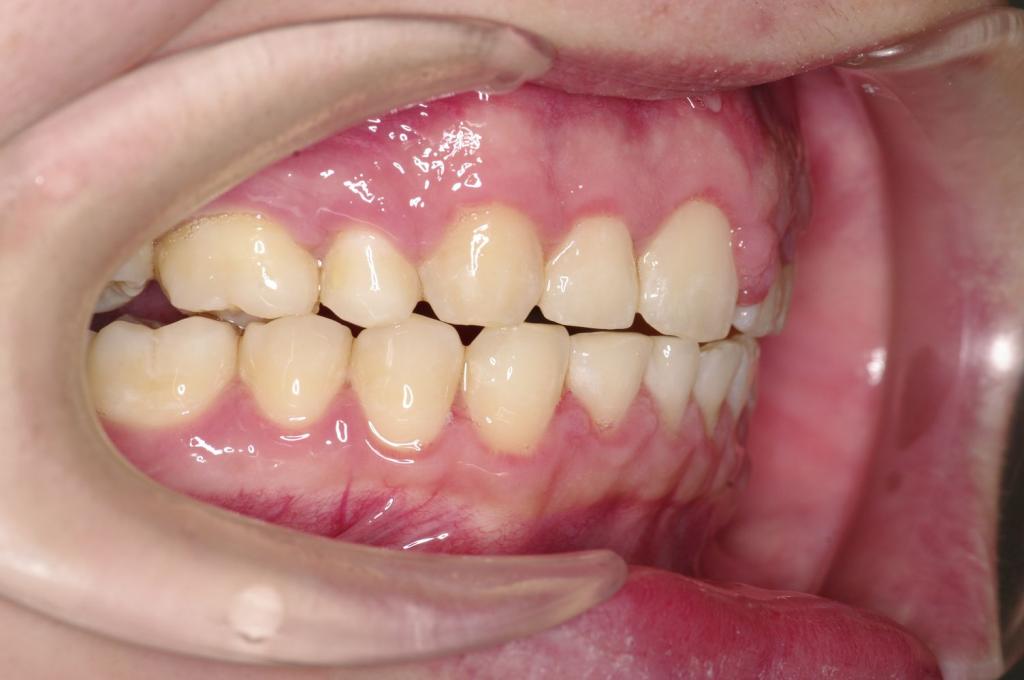

前歯、出っ歯・開咬の矯正治療

(治療期間、治療前後写真、治療方法、費用)WORKS